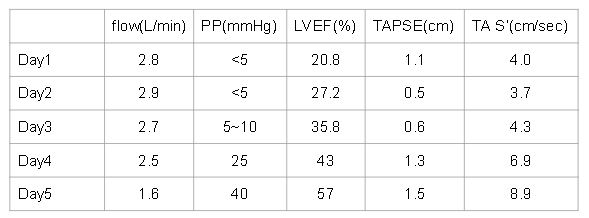

Cardiac output : Average 2.13 ( L/min ) by thermodilution

RPAW: 19 mmHg

MPA: 28/22 mmHg

RA 26/22 mmHg

We report a youngwoman with fulminant myocarditis, who survived with temporary Impella CP® support. An initial ECG showed ST elevation in V1 and aVR, indicatingpossible right ventricular involvement. For circulatory support, wechosed Impella CP® because VA-ECMO would increase afterload, leadingto pulmonary edema and poor LV recovery. Even RV was involved withimpaired RV function, her clinical condition remained stable underthe treatment guided by PAC. By day 3, her cardiac function hadimproved much, and the Impella CP® was removed on day 5. The patient wasdischarged on day 11. One-month follow-up showed full RV and LVrecovery.